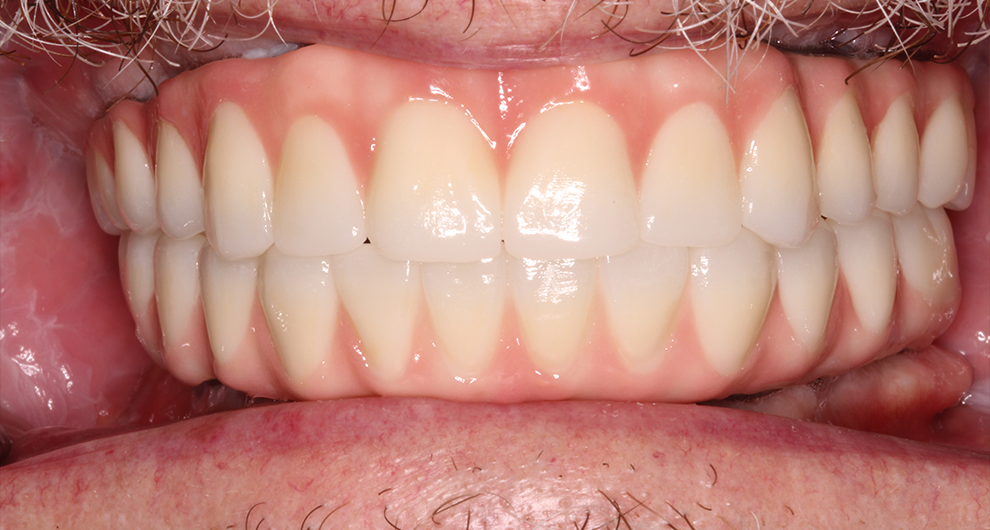

Click and drag the lines to reveal before and after

Before treatment After treatment

Before treatment

After treatment